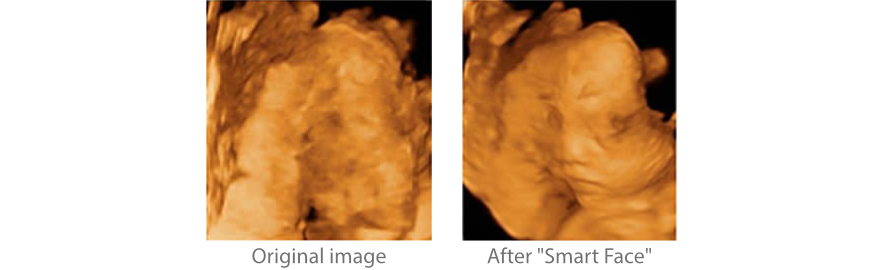

Smart Face

Yeni Z50, tek dokunu?la fetal y├╝z i?in h?zl? ve ak?ll? optimizasyon sa?lar. Hacim verilerinde okl├╝zyonlar? an?nda kald?rabilir, istenmeyen g├╝r├╝lt├╝ bilgilerini ortadan kald?rabilir ve minimum i?lemle fetal y├╝z├╝n optimum g?r├╝n├╝m├╝n├╝ olu?turabilir.